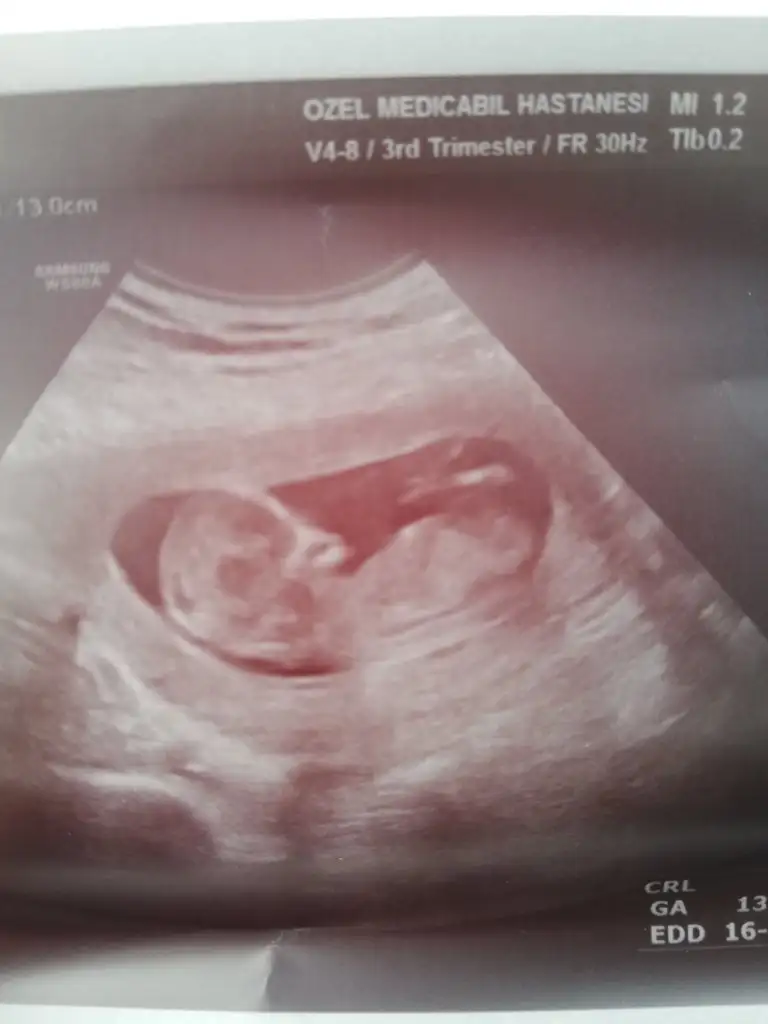

Net degil kız gibi sanki nubu yakınlaşınca bozuluyor yani eminde değilimMerhaba yorumlayabilen ler rica etsem usg yi yorumlar mısınız? 12+4 günlük karından usg